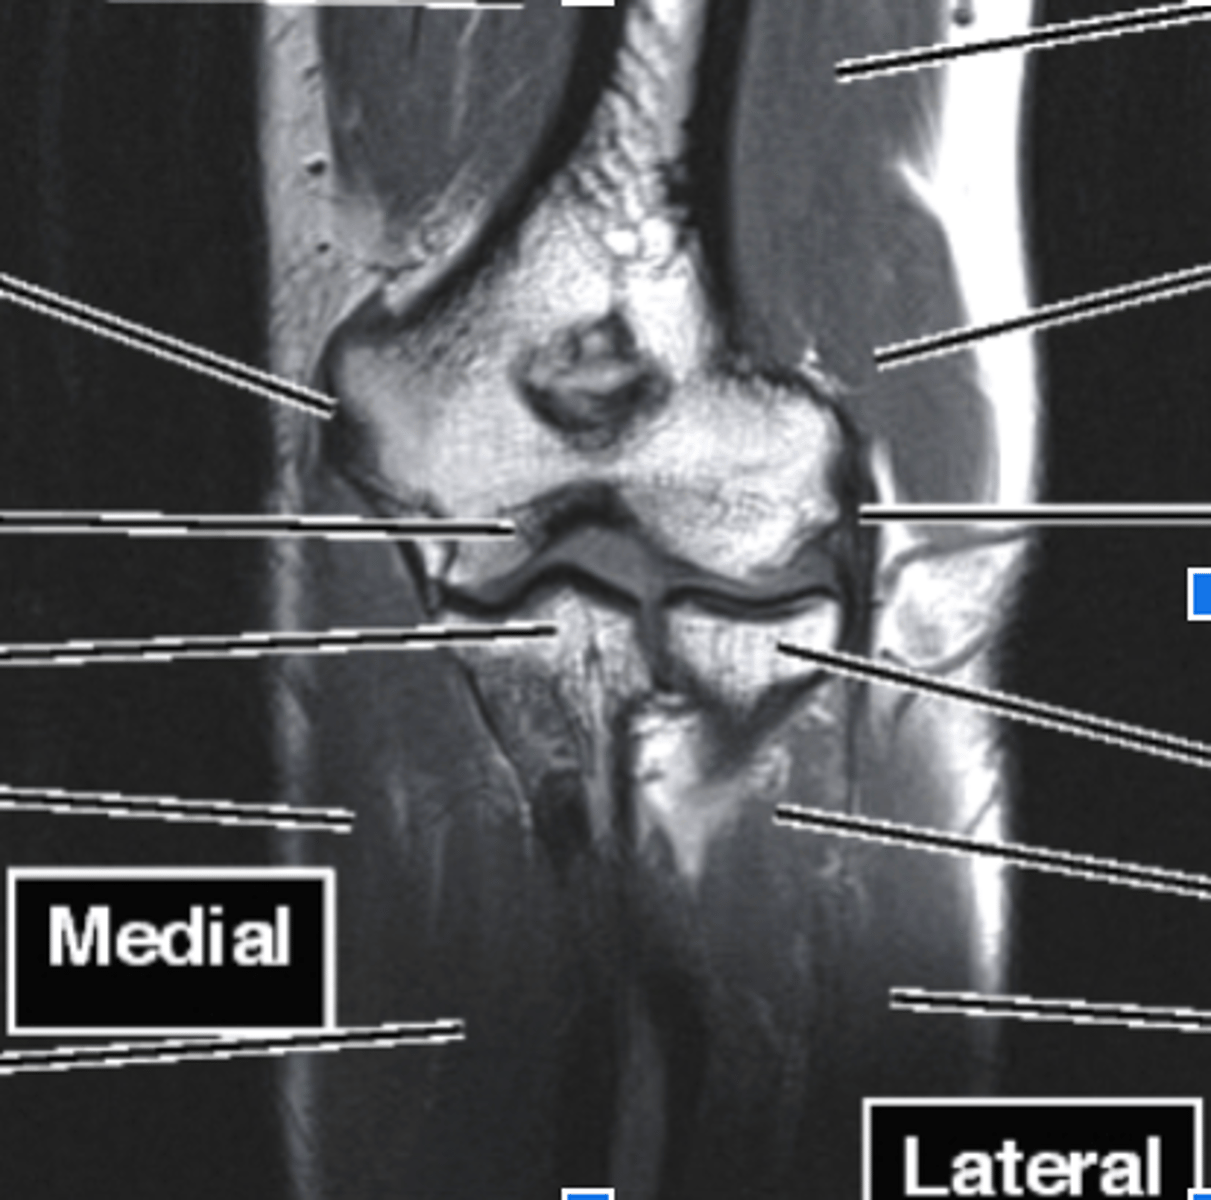

Elbow MRI

what type of imaging is this?

humerus

what does this pink line point to?

ulna